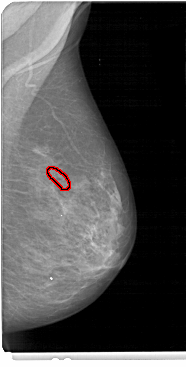

A_1465_1.RIGHT_CC

RIGHT_CC LINES 5416 PIXELS_PER_LINE 2701 BITS_PER_PIXEL 12 RESOLUTION 43.5 OVERLAY

FILE: A_1465_1.RIGHT_CC.OVERLAY

TOTAL_ABNORMALITIES 1

ABNORMALITY 1

LESION_TYPE CALCIFICATION TYPE FINE_LINEAR_BRANCHING DISTRIBUTION LINEAR

ASSESSMENT 5

SUBTLETY 3

PATHOLOGY MALIGNANT

TOTAL_OUTLINES 1

BOUNDARY